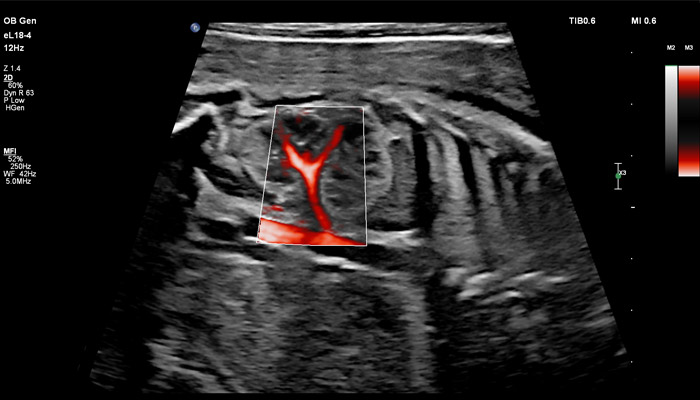

Точная оценка состояния плаценты важна при определении сроков родоразрешения, а также при планировании хирургических вмешательств. Изображения показывают нормальный миометрий и четкую границу с плацентой. С визуализацией микрокровотока (MFI) хорошо представлены дугообразные артерии матери, спиральные артерии, а также ветвящиеся ворсинчатые артерии, что подтверждает нормально развитую сосудистую систему.

Клинические исследования, проведенные экспертами детской больницы штата Аризона (США) во главе с Д-ром Льюсом Гонкалвсом с целью определения наличия нормальной сосудистой структуры плаценты при подозрении на ее патологию, показали, что инновационная технология сверхширокополосной PureWave матрицы датчика eL18-4 способна изменить привычный способ, которым врачи интерпретируют нормальный и аномальный сосудистый поток в плаценте.